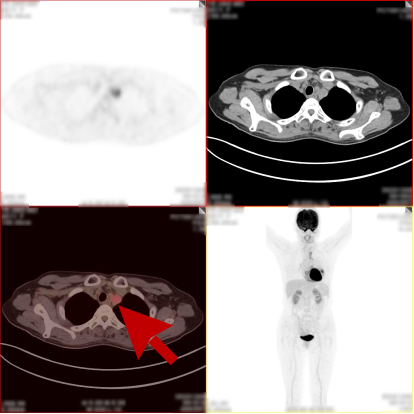

病史:女,51岁,左侧胸腔肿物约3-4年,干咳伴左侧胸痛1个月余,自服药物不能缓解。2023.12.6 CT 显示左侧胸腔及纵隔内肿块,考虑肿瘤性病变,胸膜来源低度恶性肿瘤(胸膜间皮瘤)可能。无其他病史,进食可,二便可,今年以来有体重减轻,为鉴别病灶良恶性申请PET/CT检查。

PET/CT检查所见

PET/CT诊断意见:

1、左侧胸腔内混杂密度肿块,实性组织代谢轻中度增高,考虑间叶组织来源低度恶性肿瘤,病灶内部分组织坏死,与左侧胸膜粘连并向纵隔内生长;

2、纵隔(1L、2L、3A、6、8R 组)及左侧锁骨上窝多发淋巴结转移灶;

3、胸 8 椎体左份结节状高代谢病灶,考虑骨转移灶。

PET/CT活检病理:恶性畸胎瘤